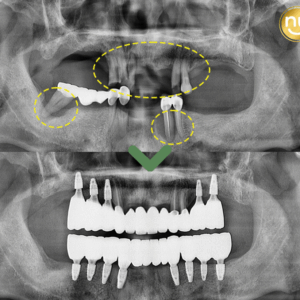

울산안아픈치과 신경치료 후 염증 치아재식술로 해결해요! 안녕하세요. 울산안아픈치과 뉴욕연합치과입니다. 임플란트가 워낙 보편화되고 선호하는 분들이 많아지고 있지만, 자연치아를 살리고자 하는 수요도 급상승하고 있는 추세입니다. 위 환자분은 충치가 많이 진행되어 신경치료한 치아를 사용하고 있었습니다. 하지만, 오랜 기간이 지나 치아 뿌리 끝에 염증이 생겨 발치를 권유받았는데요, 발치를 하더라도 치아 뿌리만 손상 더보기…